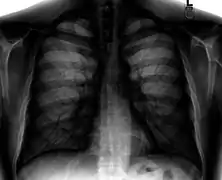

A normal posteroanterior (PA) chest radiograph of someone without any signs of injury. Dx and Sin stand for "right" and "left" respectively.

Different views (also known as projections) of the chest can be obtained by changing the relative orientation of the body and the direction of the x-ray beam. The most common views are posteroanterior, anteroposterior, and lateral. In a posteroanterior (PA) view, the x-ray source is positioned so that the x-ray beam enters through the posterior (back) aspect of the chest and exits out of the anterior (front) aspect, where the beam is detected. To obtain this view, the patient stands facing a flat surface behind which is an x-ray detector. A radiation source is positioned behind the patient at a standard distance (most often 6 feet, 1,8m), and the x-ray beam is fired toward the patient.

Required projections can vary by country and hospital, although an erect posteroanterior (PA) projection is typically the first preference. If this is not possible, then an anteroposterior view will be taken. Further imaging depends on local protocols which is dependent on the hospital protocols, the availability of other imaging modalities and the preference of the image interpreter. In the UK, the standard chest radiography protocol is to take an erect posteroanterior view only and a lateral one only on request by a radiologist.[5] In the US, chest radiography includes a PA and Lateral with the patient standing or sitting up. Special projections include an AP in cases where the image needs to be obtained stat (immediately) and with a portable device, particularly when a patient cannot be safely positioned upright. Lateral decubitus may be used for visualization of air-fluid levels if an upright image cannot be obtained. Anteroposterior (AP) Axial Lordotic projects the clavicles above the lung fields, allowing better visualization of the apices (which is extremely useful when looking for evidence of primary tuberculosis).